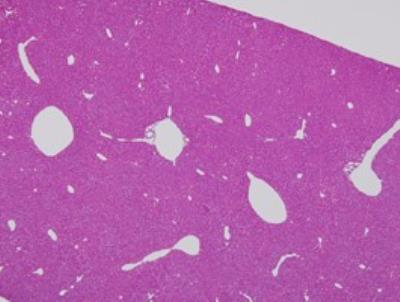

I think these maybe brain cells.

BRAIN CELLS:

All of these photos are not mine. the labels on the larger photo above these two are not mine either.

Brain cells found in my slides:

A lot of these look a little bit different but I think these are brain cells.